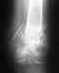

На снимках нет ни перекоса таза, который требовал бы коррекции, ни значимого укорочения.

Операции типа "Удалили части порванной губы" не меняют положение вертлужной впадины и головки бедренной кости, соответственно, не приводят к перекосу таза и укорочению.